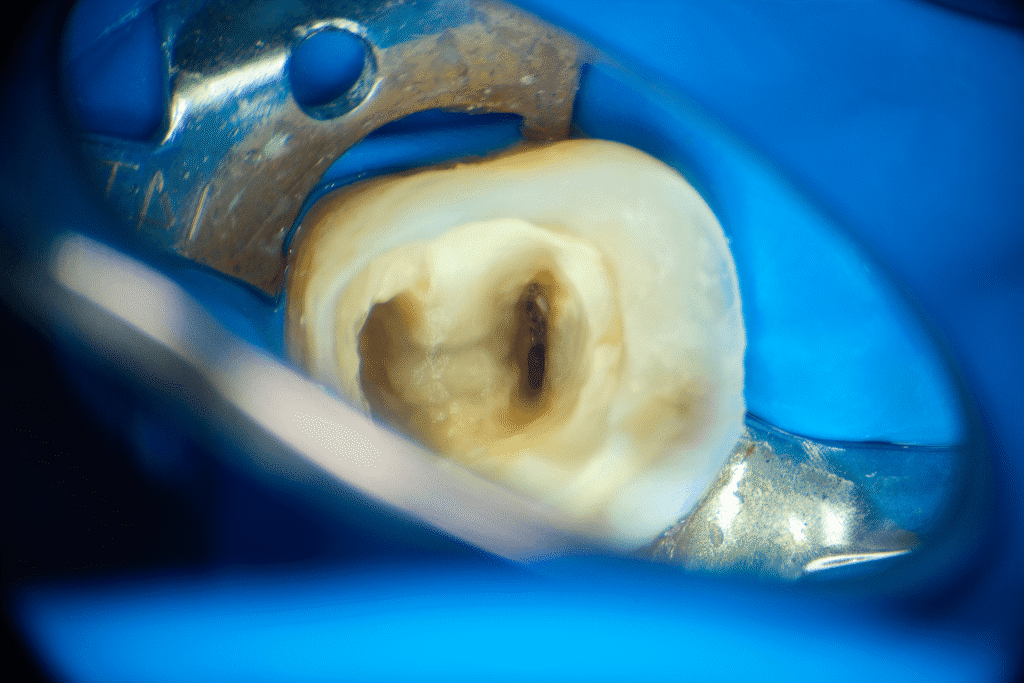

Pacjentka lat 54 trafiła do mojej kliniki skierowana z innego gabinetu celem leczenia endodontycznego zęba 46. W badaniu stwierdziłem znaczny zanik światła kanału korzeniowego. W badaniu tomograficznym stwierdziłem całkowity zanik kanału korzeniowego w strefie mezjalnej. Korzeń dystalny mimo widocznego światła kanału na CBCT, widoczne było wiele zwapnień w środkowej części kanału. Po wykonaniu dostępu endodontycznego zlokalizowałem materiał wypełniający kanał pozostawiony po poprzednim nieskutecznym leczeniu endodontycznym. Do usunięcia wykorzystałem laser 2780nm (25mJ/puls). W kolejnych etapach instrumentacji wspomaganie ultradźwiękami oczyściłem strefy mezjalną i dystalną. Instrumentacja themo-

mechaniczna polegała na zastosowaniu protokołu ciągłej chelacji wraz z użyciem lasera

2780nm z końcówką płaską (50mJ/puls) celem udrożnienia przestrzeni endodontycznych. Po wstępnym uzyskaniu drożności zastosowałem instrumentację maszynową wspomagająco celem udrożnienia przestrzeni. Finalnie obturacja z zastosowaniem ćwieków gutaperkowych kalibrowanych na WL i uszczelniacza na bazie krzemianów wapnia. W przeciwieństwie do tradycyjnych uszczelniaczy, nie wymaga mieszania, co eliminuje błędy w proporcjach i zapewnia powtarzalną konsystencję. Jest materiałem wysoce biokompatybilnym i bioaktywnym. Finalnie zamknięto ząb odbudową kompozytową tymczasową i skierowano na dalsze leczenie protetyczne do gabinetu kierującego pacjenta.